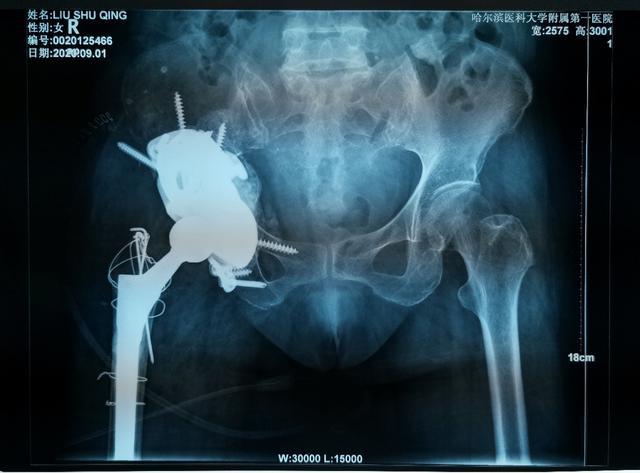

對于復(fù)雜髖關(guān)節(jié)翻修多為高齡患者,由于骨缺損巨大、骨質(zhì)疏松等因素,存在手術(shù)難度大、手術(shù)費用高等難題。近日,哈醫(yī)大一院骨科一病房3D打印團隊,應(yīng)用3D打印技術(shù),通過術(shù)前打印骨骼模型進行模擬假體安裝,成功為一名70歲,全髖關(guān)節(jié)置換術(shù)后15年,髖臼骨缺損巨大,髖臼上部坐骨、髂骨存在巨大空洞型缺損的患者實施了我省首例金屬3D打印三翼髖臼假體(Triflange)+股骨柄假體髖關(guān)節(jié)翻修術(shù),為患者更換了一個新的、穩(wěn)定的髖關(guān)節(jié)。目前患者已康復(fù)出院。

70歲的劉阿姨十五年前因股骨頭壞死進行了全髖關(guān)節(jié)置換手術(shù)。五年前右腿開始有明顯的縮短,髖部疼痛也逐漸加重,來到哈醫(yī)大一院時已經(jīng)無法行走。經(jīng)影像檢查,患者十五年前采用水泥固定髖臼杯,金屬頭和聚乙烯髖臼杯十?dāng)?shù)年的摩擦產(chǎn)生的聚乙烯碎屑已經(jīng)導(dǎo)致髖臼巨大的骨缺損,假體上移,不僅髖臼,甚至坐骨,髂骨都有骨溶解,屬于Paprosky·3B型髖臼側(cè)骨缺損。此類疾病的治療主要采用三翼髖臼假體(Triflange)。由于患者髖臼骨缺損巨大,特別是在髖臼上部存在巨大的空洞型缺損,傳統(tǒng)的Triflange假體不能滿足劉阿姨髖臼的穩(wěn)定支撐和重建,且患者骨質(zhì)疏松,傳統(tǒng)假體骨長入能力難以滿足要求。

骨科一病房數(shù)字骨科負責(zé)人耿碩教授在詳細了解患者情況后,決定為患者進行個性化的金屬3D打印技術(shù)。定制化3D打印髖臼Triflange假體相比于傳統(tǒng)假體有以下優(yōu)點: 1、3D打印Triflange假體三個翼面通過螺釘分別固定在髂骨,恥骨和坐骨上提供了穩(wěn)定的初始固定。2、金屬3D打印擁有更好的孔隙率,有助于后期骨長入穩(wěn)定固定。3、個性化的術(shù)前設(shè)計,實現(xiàn)了墊塊和臼杯一體的輕量化支撐,更好地填充上方骨缺損重建髖關(guān)節(jié)的穩(wěn)定性,此外為應(yīng)對術(shù)中可能的意外情況,還可3D打印不同大小的墊塊。

為了確保手術(shù)順利,手術(shù)前,耿碩教授根據(jù)患者的影像數(shù)據(jù),經(jīng)過三維重建,真實復(fù)原了患者的右髖關(guān)節(jié)和盆骨模型。借助這一模型,耿碩教授可以全面精準(zhǔn)地了解患者的關(guān)節(jié)結(jié)構(gòu),骨質(zhì)情況等重要信息,為術(shù)前制訂精確地手術(shù)方案提供了重要的依據(jù)。手術(shù)當(dāng)日,耿碩教授手術(shù)團隊按照術(shù)前模擬,順利的將金屬假體精準(zhǔn)地安放在髖關(guān)節(jié)內(nèi)。經(jīng)過一周的康復(fù),患者已順利下地行走并康復(fù)出院。